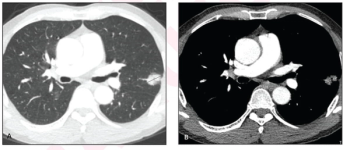

In comparison to pure solid nodules in patients with non-small cell lung cancer (NSCLC), nodules with a minor ground glass opacity component were associated with over a 38 percent higher rate of recurrence-free survival.